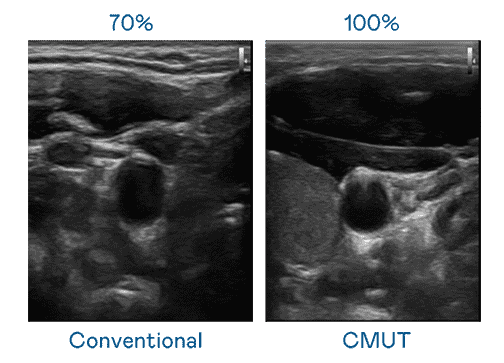

CMUT 技术是一种用电容式微机电元件来产生超音波讯号的技术。。与传统 PZT 压电式技术相比,,CMUT 频宽增加 30%,,,更宽频的超音波讯号让影像解析度大幅提升,,是实现高影像品质医疗超音波扫描、、、促进精准医疗发展的关键技术。。。

超音波影像的解析度高低,,首先取决于探头能发出的讯号频宽。。万利 CMUT 可提供高清晰的超音波讯号,,,,提供高频宽、、高灵敏度、、、影像纹理细节更高的超音波影像,,,,协助医护人员缩短影像判读时间及利用精准的医疗影像进行诊断。。。